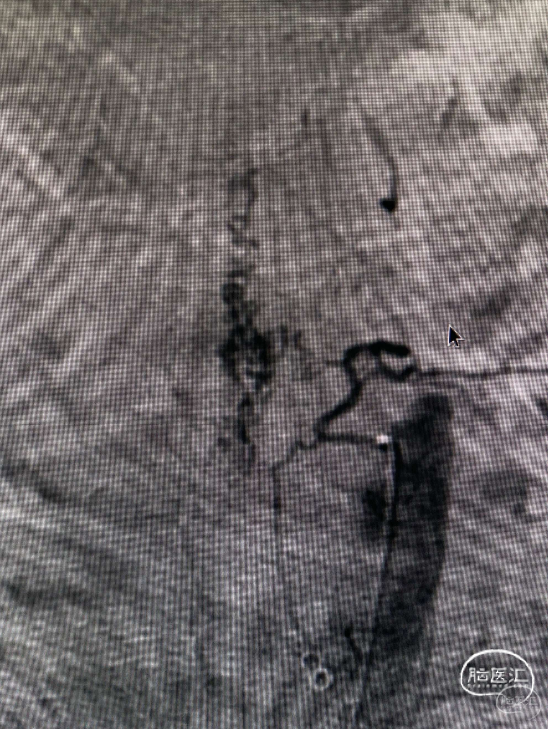

60多岁的老人家,背痛好几年,双下肢活动障碍,大小便控制不了几个月,做检查发现是硬脊膜动静脉瘘(脊髓膜上的动静脉短路),很容易被误诊为椎间盘突出的疾病。

确定病变位置,定位清楚。

打开就可以找到瘘口。

荧光造影确定病变位置,给予夹闭。

瘘口消失,早显迂曲的静脉也不显影了。很好的解决病变。第二天患者就感觉胸部的束缚感有明显的缓解。